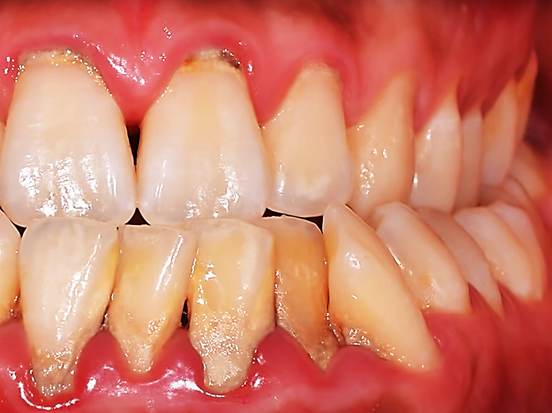

치석은 침이 많이 나오는 침샘 부근에 있는 치아에 주로 많이 생깁니다.

혀밑 침샘이 있는 아랫니 안쪽

그리고 귀밑 침샘이 있는 윗니 어금니 바깥쪽에 많이 생깁니다.

치석은 잇몸질환의 가장 근본적인 원인이고 첫 번째 원인이 됩니다.

치석 표면은 거칠어서 프라그가 쉽게 붙을 수 있는 장소가 됩니다.

프라그는 세균덩어리입니다. 잇몸질환을 유발하는 주된 원인이기 때문에 프라그가 잘 생길 수 있는 치석을 제거하는 관리는 꼭 필요합니다.

잇몸과 치아 경계에 치석이 생기면 염증이 생기기 쉽고 이로 인해 잇몸이 민감해져 혈관이 확장되어 통증과 출혈이 생길 수 있습니다.